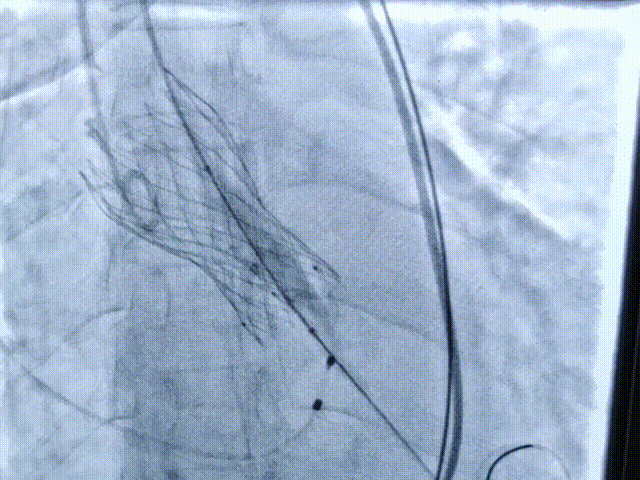

第二次释放位置良好

瓣膜打折

球囊后扩

最终位置完美,无瓣周漏